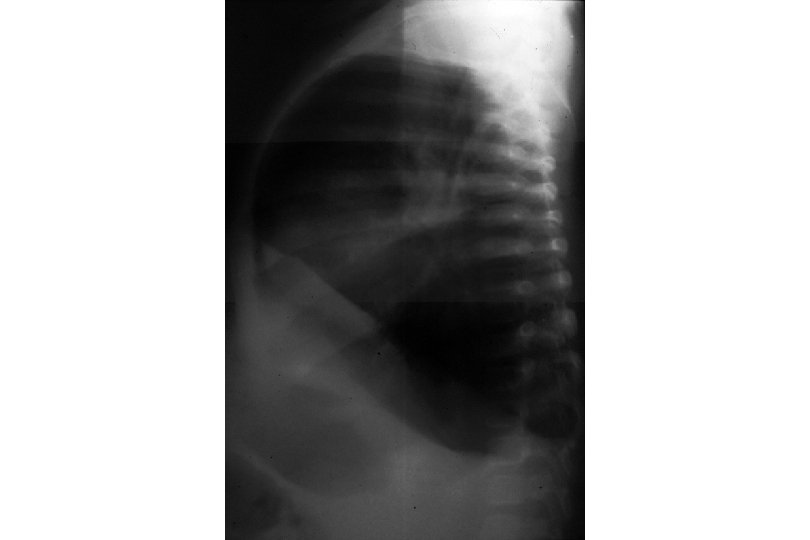

Signs of Respiratory Distress and Failure signs of respiratory distress: - tachypnea, tachycardia - retractions (intercostal, superclavicular, nasal flaring) - grunting signs of respiratory failure - altered mental status - poor color - hypotonia

Infant with Increased Respiratory Effort Note use of intercostal and accessory muscles